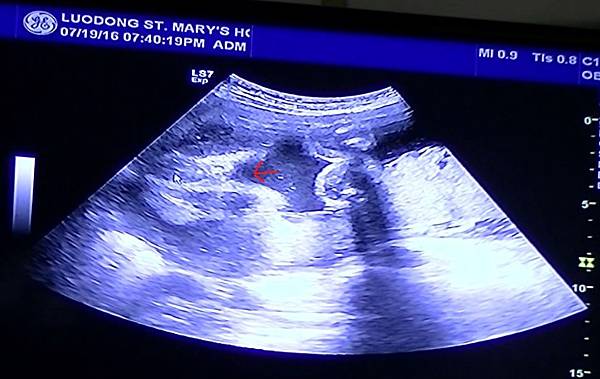

小小長長的一顆胚胎像個茄子(當然沒有那麼長, 只是跟萱萱比起來較長型)我記得以前萱萱是比較橢圓形像雞蛋

測了一下大小約9W1.39cm哈哈有照到就好粉開心

再下一次產檢照到心跳瞜然後看他小小的揮舞著手手腳腳真是可愛的不得了

![20160224_163930[1].jpg 20160224_163930[1].jpg](https://pic.pimg.tw/thedancer/1468484675-2975074373_n.jpg?v=1468484681)